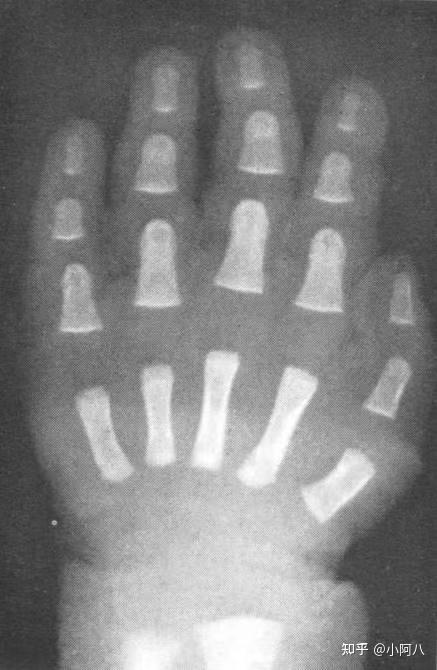

手掌骨骺线闭合区别图 第1页

骨骺线闭没闭合对比图

骨骺线闭合怎么看骨骺线闭合怎么看图